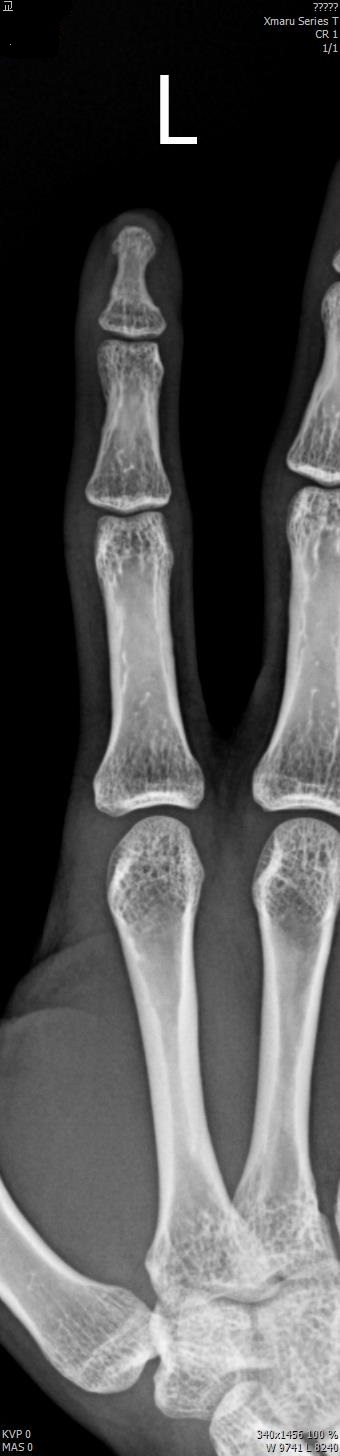

2017년 2월 14일 수지접합 ( 좌측 2수지 절단 치료 전, 후 모습)

2017년도 224일 당시 ( 외국인 교 **)께서 기계에 전달되어 본원 방문함.

올 해 19일 약 1년여간 수지접합 치료 전,후 과정을 올립니다.